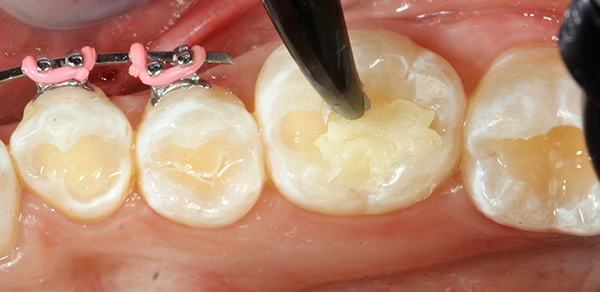

I then filled the preparation with bulk fill composite (Fig. 4). The composite of choice for this case was SonicFill™3 (Kerr), which is a sonic-activated bulk fill composite.

SonicFill 3 replaces conventional time-consuming, multi-stage layering techniques used with other composites while providing improved adaptation. It’s easy to handle, sculpt and polish as well as simple to extrude with a specialized handpiece (SonicFill Handpiece, Kerr) during placement.

I chose this material because it provides better adaptation to margins and internal walls. SonicFill 3 contains rheological modifiers that react to the sonic energy applied during placement, reducing viscosity to increase flowability to all cavity surfaces. Most cavities are filled in seconds.

The low shrinkage stress this composite provides ensures lasting marginal integrity. Lower shrinkage stress can lead to void- and gap-free procedures and better outcomes.

Its optimized formula is slump-free. Once the sonic energy is removed, the composite reverts to a viscous, pliable state ideal for contouring and polishing. The nano-scale zirconsil (zirconium oxide + silica oxide) filler system allows the practitioner to achieve excellent gloss, wear resistance and reliability.

SonicFill 3 also has a high depth of cure. Refractive index matching and an enhanced curing mechanism allow polymerization depths up to 5mm in a single step, while still retaining opacity for esthetically-pleasing finishes.4

Composite sculpting was achieved with a generic composite instrument (Fig. 5). All restorations were then cured with the Demi Plus curing light for 40 seconds each (Fig. 6).

Fig. 5 Fig. 6